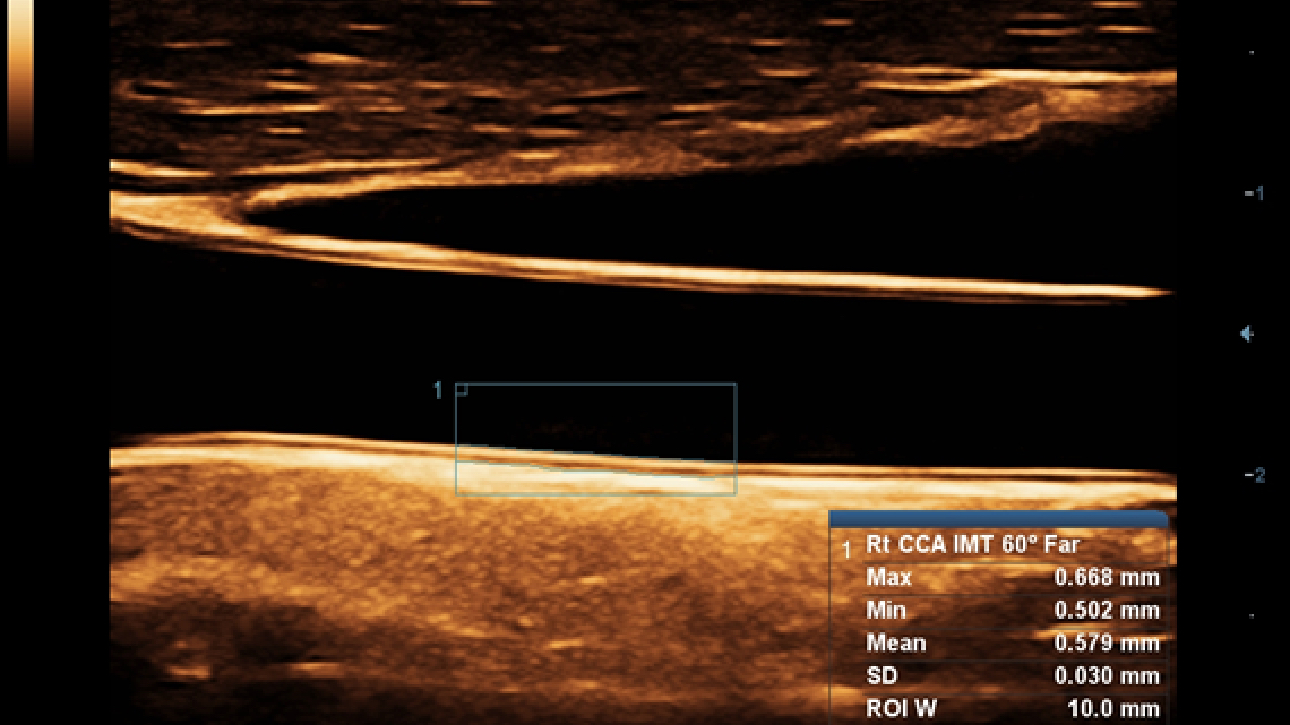

X-Insight es la soluci├│n intuitiva para una mejor visualizaci├│n.

La nueva soluci├│n de Mindray es una excelente transformaci├│n desde la continua comprensi├│n de las necesidades cl├Łnicas del usuario, combinada con la evoluci├│n de la tecnolog├Ła de los ultrasonidos m├Īs puntera. Repleto de vitalidad, con el ├║nico objetivo de visualizar el futuro y evitar los l├Łmites, el ec├│grafo DC-60Exp con X-Insight est├Ī constantemente mejorando con una escalabilidad aumentada. Como un socio personal, el equipo de ultrasonidos DC-60 Exp con X-Insight se centra en lo que verdaderamente importa, ayudando al usuario a administrar su pr├Īctica cl├Łnica con facilidad y seguridad.

Bas├Īndose en una profunda comprensi├│n de las necesidades del usuario, el sistema de ultrasonidos DC-60 Exp con X-Insight est├Ī dise?ado para ofrecer una alta eficiencia con im├Īgenes de precisi├│n, la cual se ve potenciada por una claridad inmediata, una inteligencia excepcional y benefici├Īndose de una c├│moda experiencia.